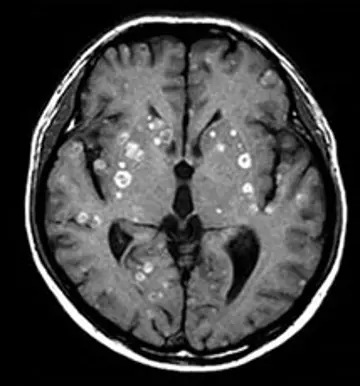

درمان متاستاز مغز با راه‌حل ژنتیکی